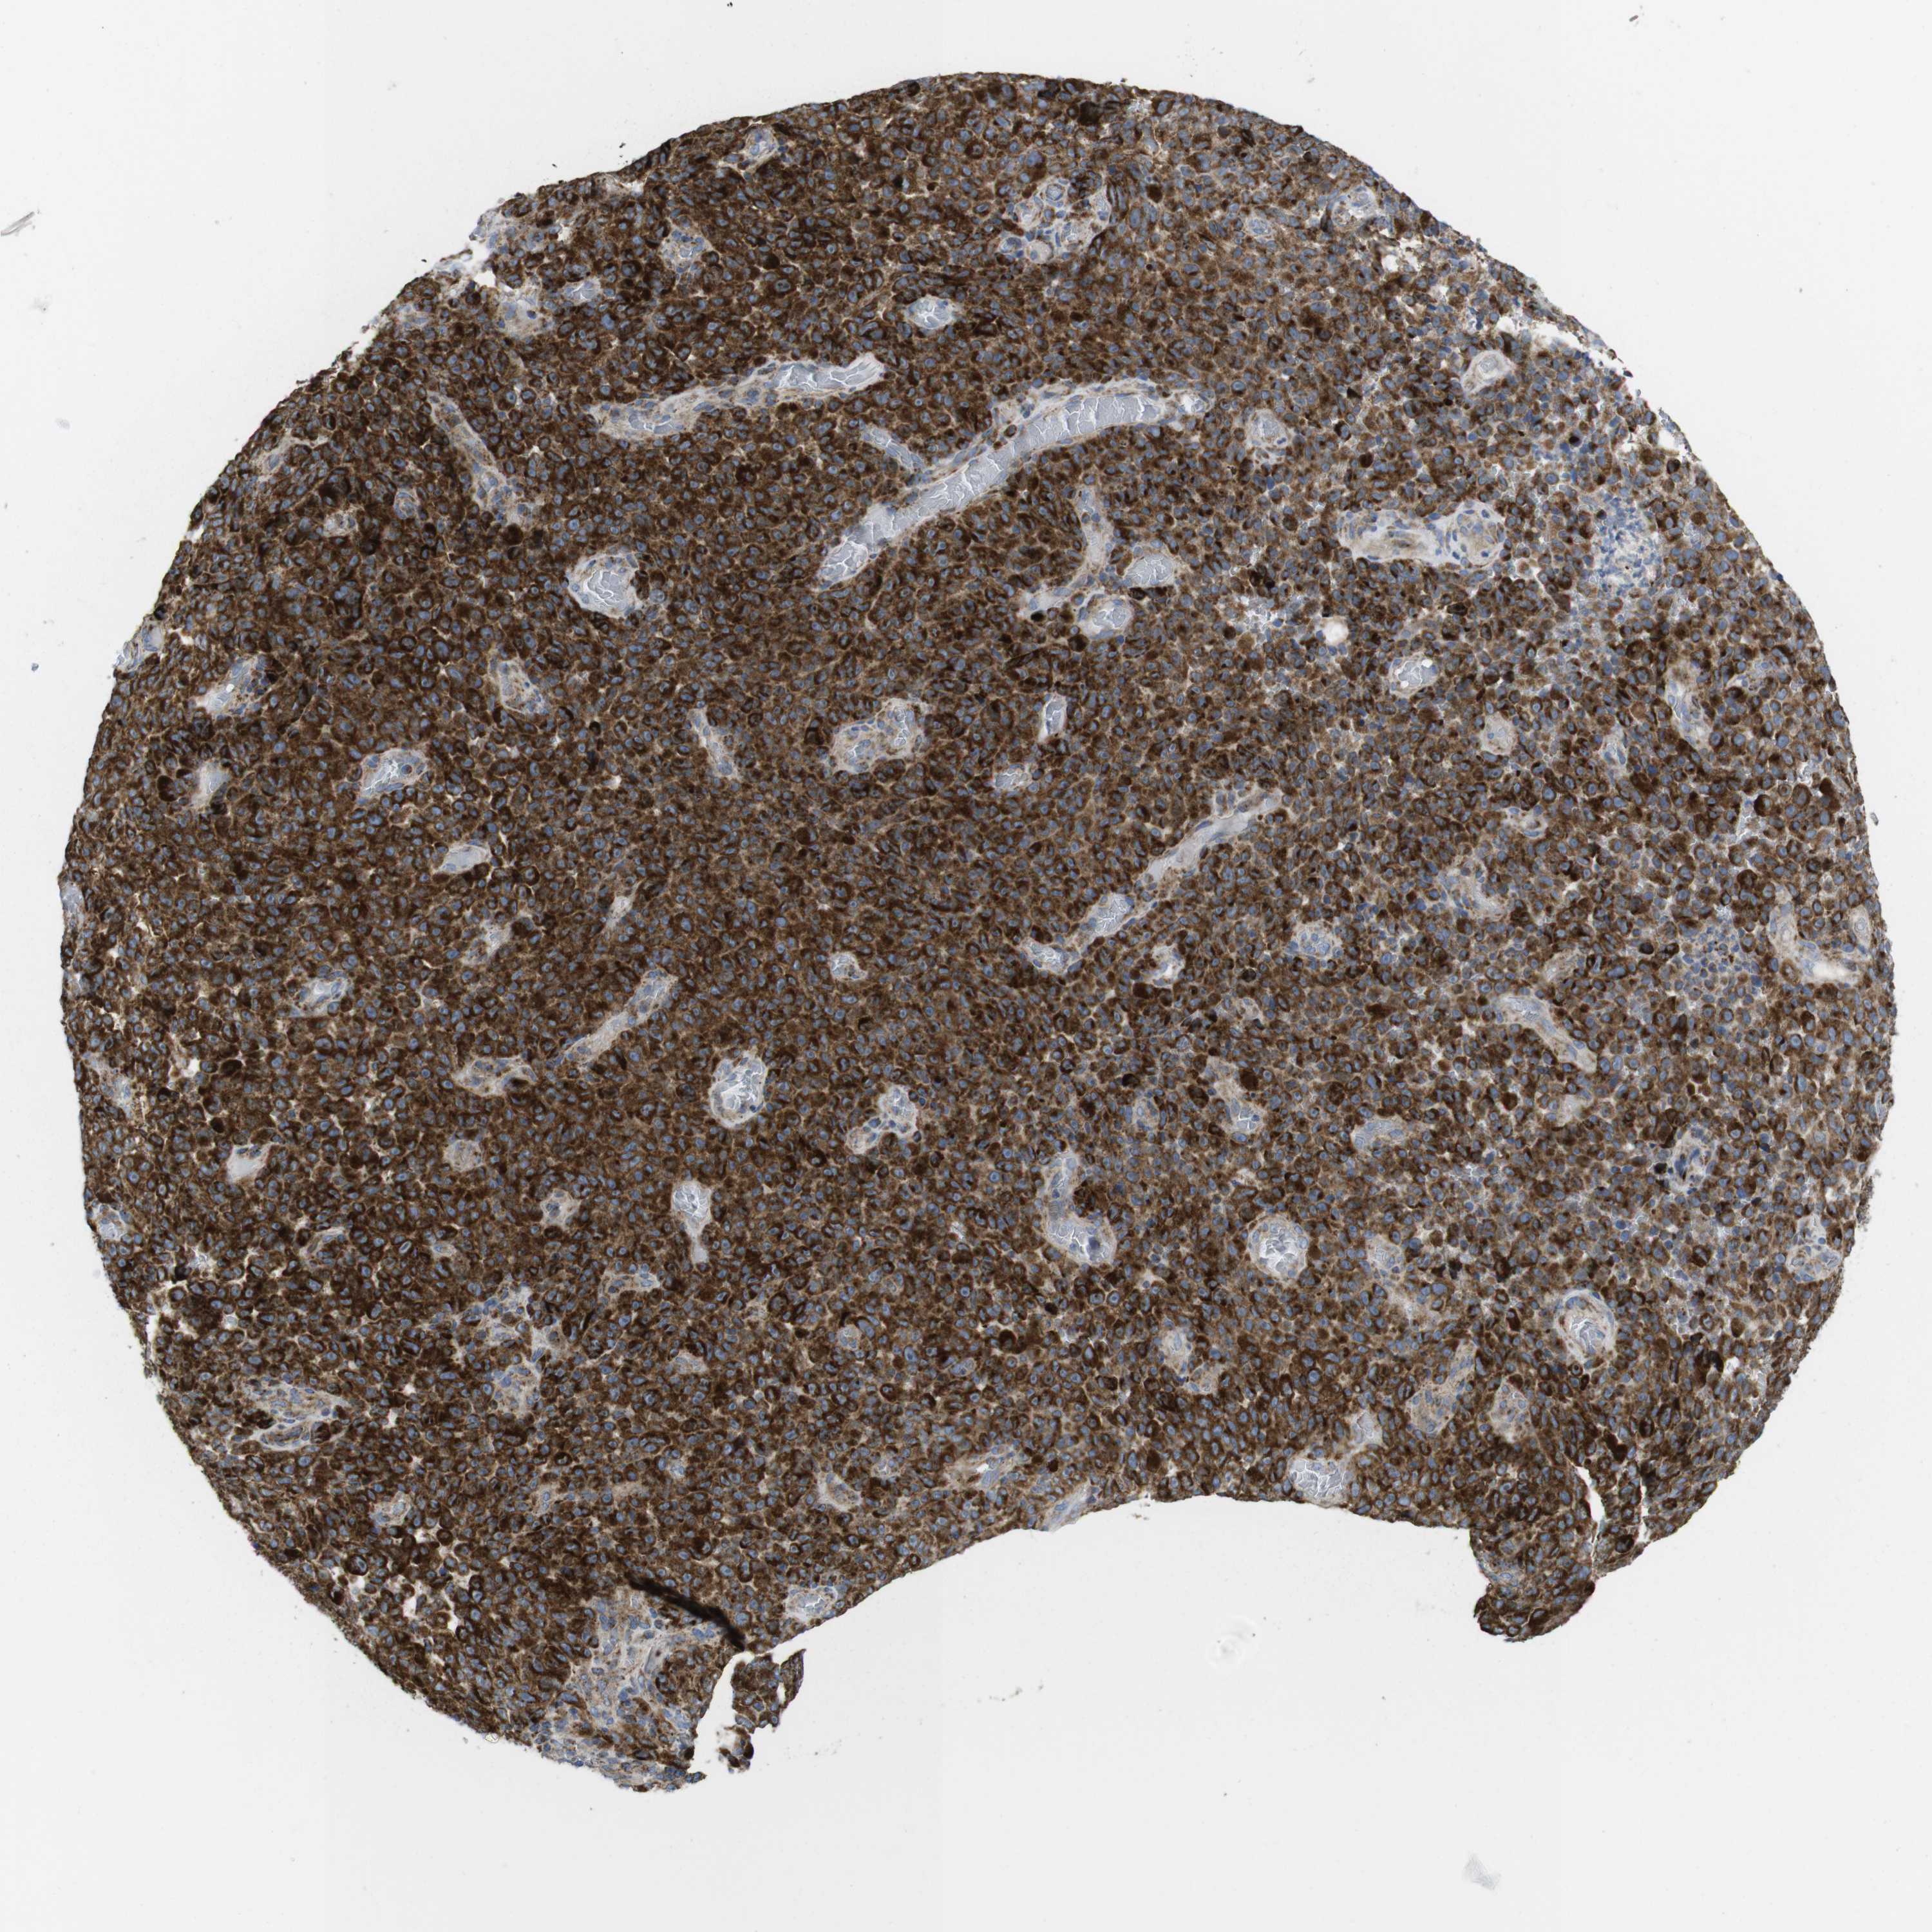

MELANOMA - Protein expressioni

A mouse-over function shows sample information and annotation data. Click on an image to view it in a full screen mode. Samples can be filtered based on level of antibody staining by selecting one or several of the following categories: high, medium, low and not detected. The assay and annotation is described here.

Note that samples used for immunohistochemistry by the Human Protein Atlas do not correspond to samples in the TCGA dataset.

Antibody stainingi

Antibody staining in the annotated cell types in the current human tissue is reported as not detected, low, medium, or high, based on conventional immunohistochemistry profiling in selected tissues. This score is based on the combination of the staining intensity and fraction of stained cells.

Each image is clickable and will lead to virtual microscopy that enables deeper exploration of all samples and also displays staining intensity scores, fraction scores and subcellular localization as well as patient and tissue information for each sample.

Antibody HPA014717

Antibody HPA024110

Staining

High

Medium

Low

Not detected

Intensity

Strong

Moderate

Weak

Negative

Quantity

>75%

75%-25%

<25%

None

Location

Nuclear

Cytoplasmic/membranous

Cytoplasmic/membranous,nuclear

Malignant melanoma, NOS

Malignant melanoma, Metastatic site